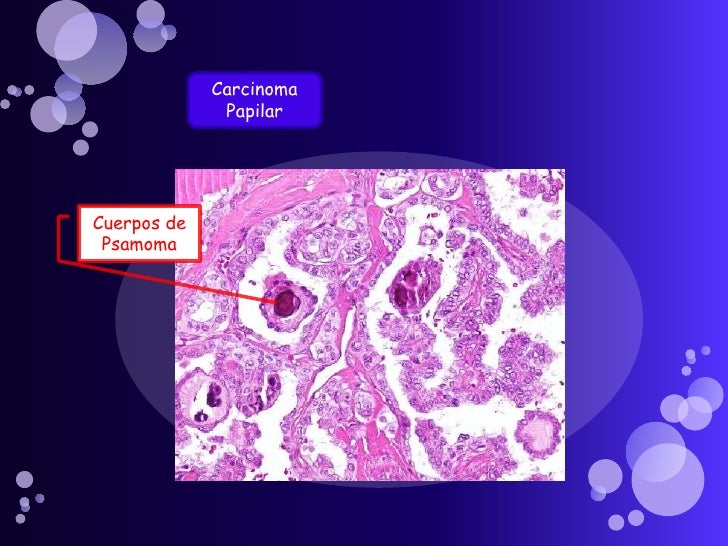

Carcinoma papilar de tiroides

V Congreso Virtual Hispanoamericano de Anatomía Patológica CARCINOMA